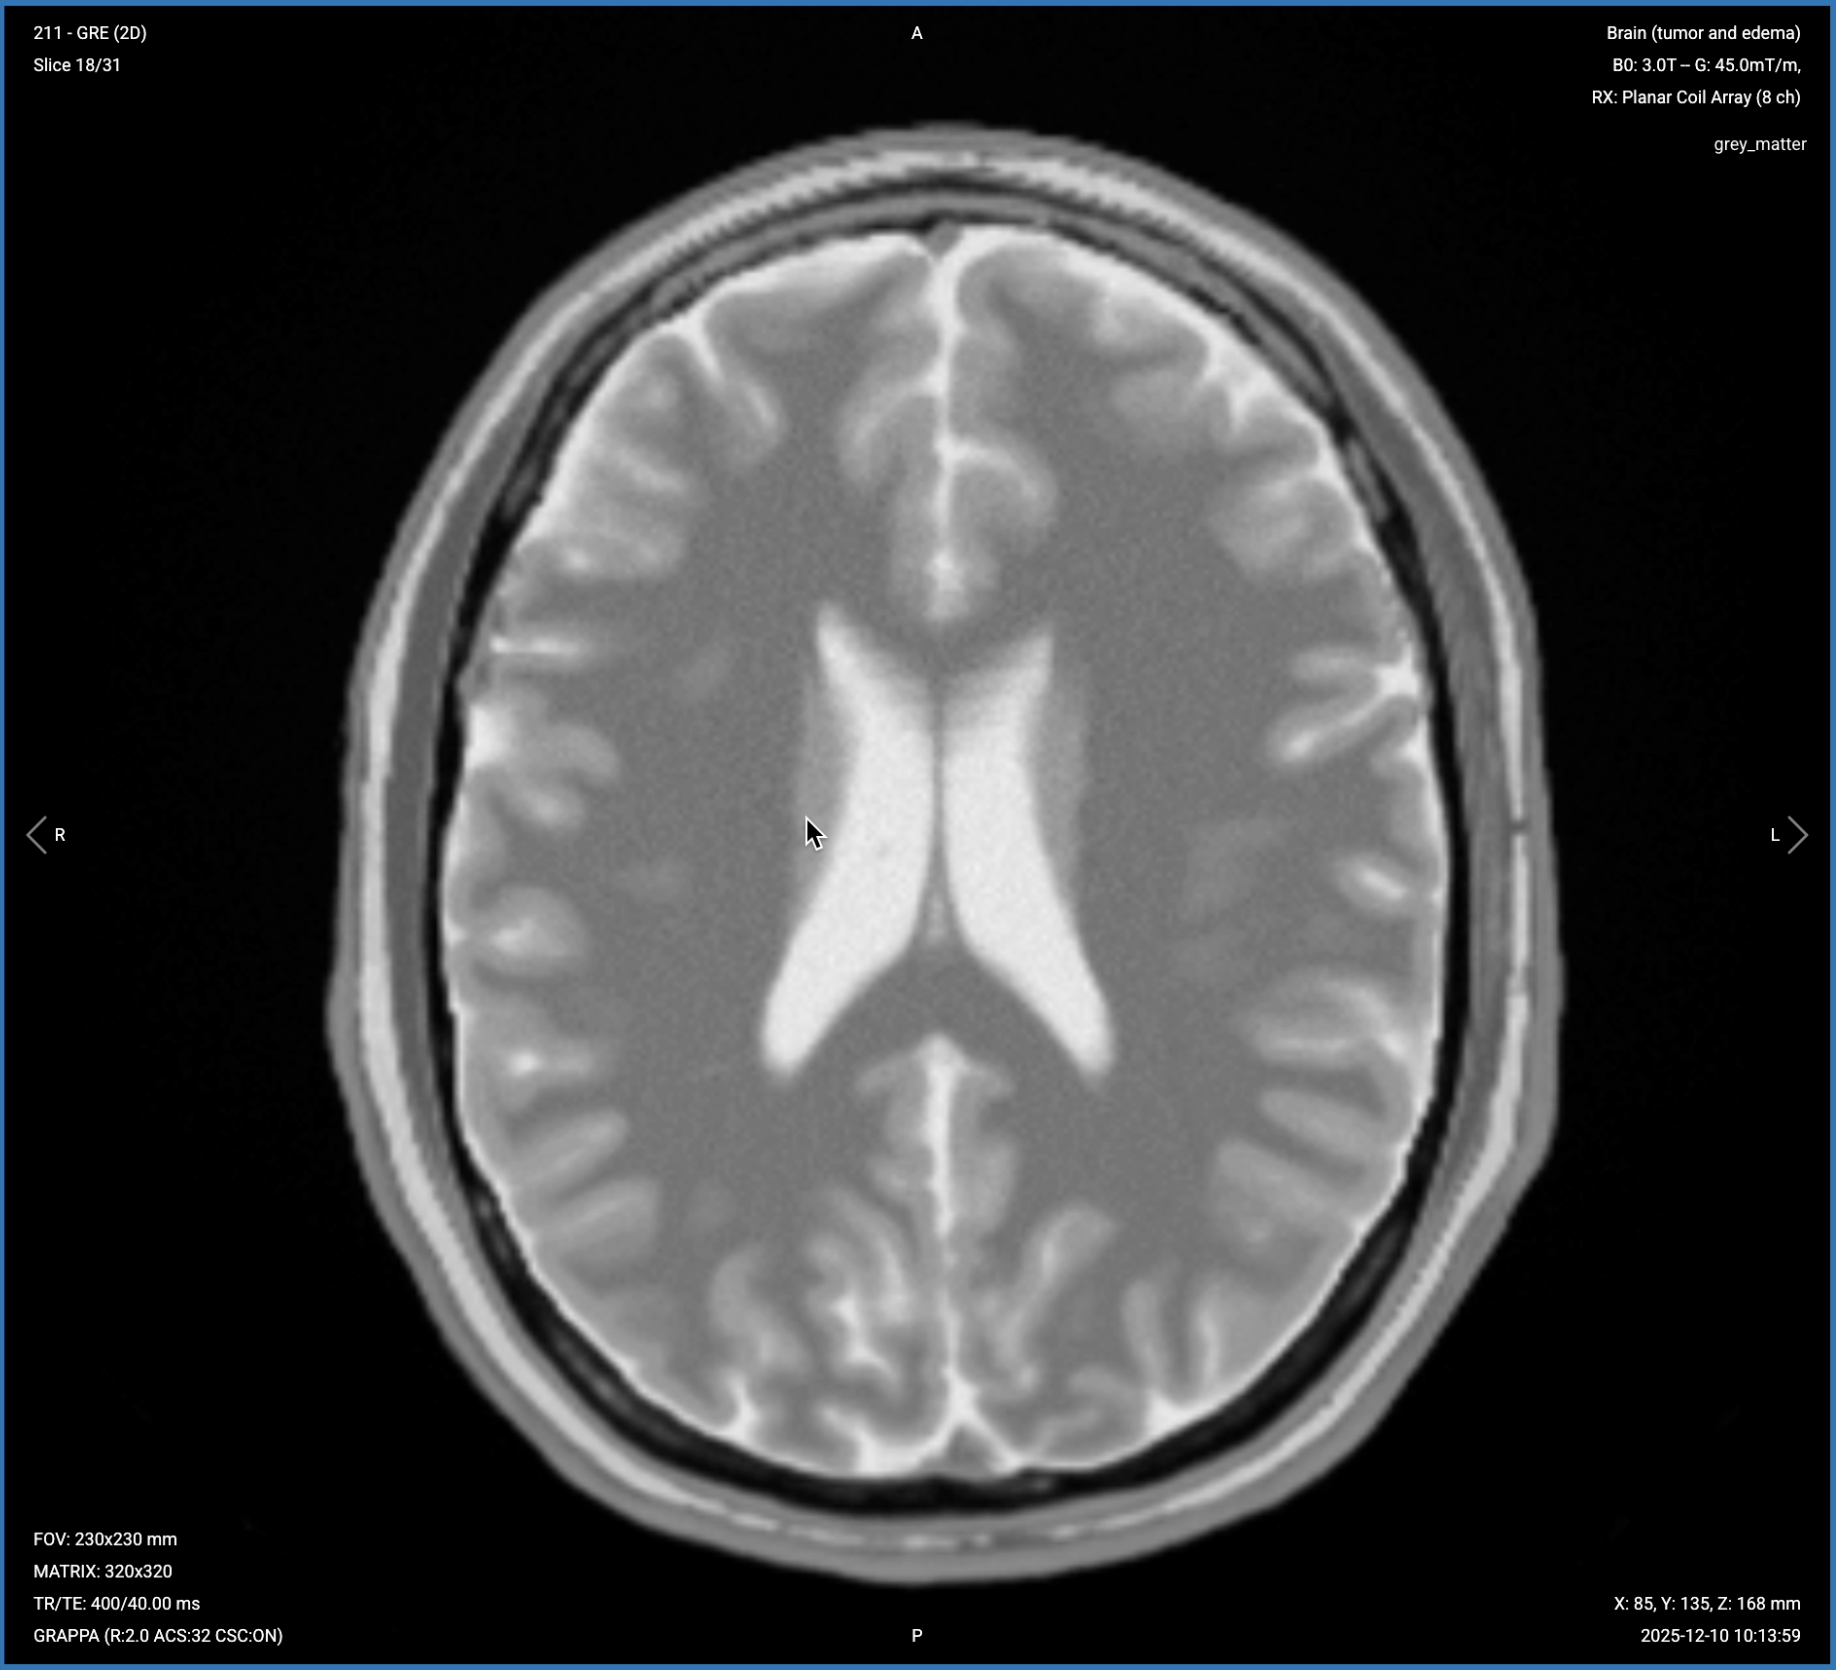

5. Planning Axial T2* Gradient Echo

✅ Correct Planning:

Correct Planning Axial T2* Gradient Echo

Planning Instructions:

• Copy the slice geometry and planning from the axial T2 TSE sequence.

• Keep the same slice angulation, coverage, and positioning to ensure images of different contrasts can be clearly compared.

Note: If higher sensitivity to blood products is needed, consider using susceptibility-weighted imaging (SWI) instead. T2* gradient echo performs adequately at 3T but SWI provides superior detection of microhemorrhages.

T2* Gradient Echo – Detects Hemorrhagic Components

T2* gradient echo is highly sensitive to magnetic susceptibility effects from blood products. Hemosiderin, deoxyhemoglobin, and other blood breakdown products cause marked signal loss, appearing as dark blooming artifacts.

In brain tumor imaging, T2* sequences help detect hemorrhagic components and calcification. Look for blooming artifacts or the dual rim sign to confirm hemorrhage or cavernoma. If there's distortion from susceptibility, it could indicate calcification or oligodendroglioma.

We acquire this sequence in the axial plane to match other sequences and allow direct comparison of hemorrhagic findings with tumor margins seen on other contrasts.

✅ Axial T2* Gradient Echo of the Brain – Correct Image Example:

Axial T2* Gradient Echo of the Brain – Correct Image Example

Things to Look for in T2* Gradient Echo:

• Blooming artifacts from blood products appearing as dark signal.

• Dual rim sign indicating specific types of hemorrhage.

• Susceptibility distortion that might indicate calcification.

• Microhemorrhages within or around the tumor.